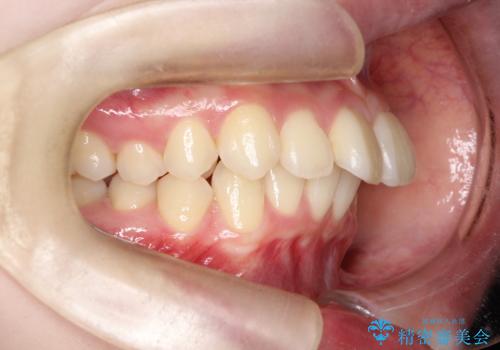

- 前歯が突き出ていることによる口元の突出感と、下顎が右側にズレていること(右方偏位)を主訴にご来院されました。

精密検査の結果、歯を並べるスペースの不足に加え、上下の歯列の正中(中心)が大きくズレていることが確認されました。突出した口元を下げ、顎の左右バランスを整えるためのスペースを確保するため、右上・左上・左下の4番目(第一小臼歯)を計3本抜歯する計画を立案。装置は、治療中の見た目にも配慮し、目立ちにくい審美ワイヤーを選択しました。